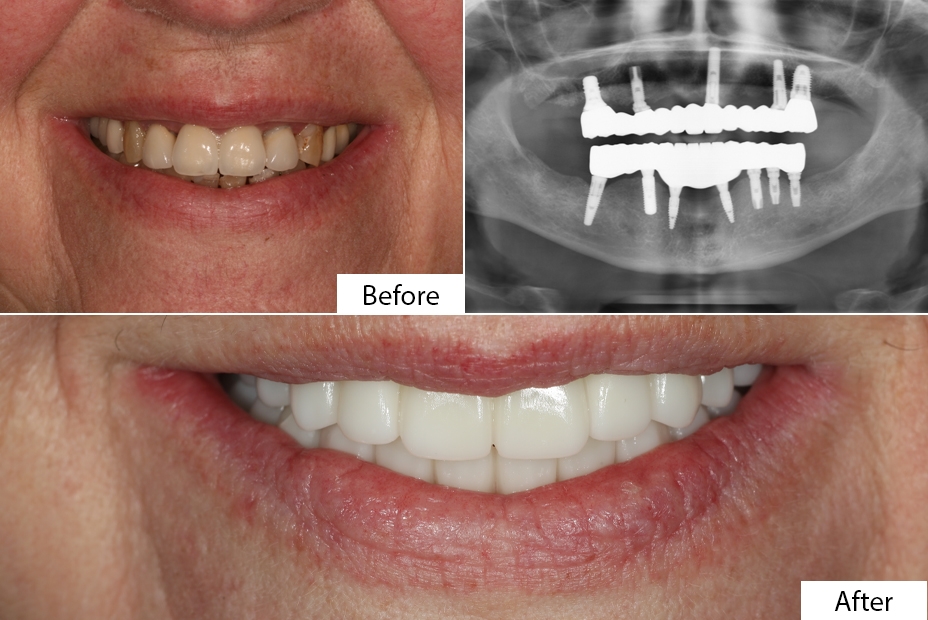

A dental implant is essentially an artificial tooth root designed to replace a missing tooth. Made from strong biocompatible materials such as a titanium implant post, it is surgically placed into the jawbone post where it naturally fuses with the bone through a process called osseointegration. This fusion provides a stable base for attaching a custom prosthesis such as a crown, bridge, or denture.

Patients often compare dental implant vs bridge vs dentures. While bridges and removable partial dentures (RPD) are cheaper, implants preserve adjacent teeth, prevent bone loss, and offer a more natural appearance and better functionality. With their long-term success rate and longevity/lifespan of implant, dental implants are considered one of the most advanced solutions in prosthodontics.

Surgical Phase – During the dental implant surgery, a titanium screw is placed into the bone. For some patients, an immediate implant may be possible, depending on the condition of the jawbone.

Healing & Recovery – Over a period of months, the osseointegration process allows the implant to bond with the bone. This healing timeline varies but is critical for long-term success.

Restorative Phase – Once healed, a permanent crown, bridge, or denture is attached. Patients may use an interim prosthesis or temporary crowns during the recovery period.

Whether opting for a single-tooth implant, multiple-tooth implant, or full-mouth implant, the procedure is designed as a comfortable treatment plan with a high success rate when performed by an experienced dentist like Dr. Usama Hayat Ghauri.